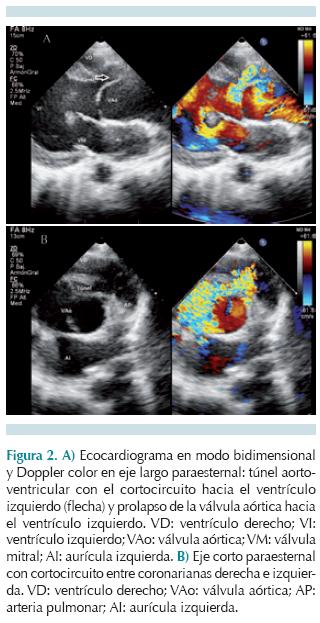

Los datos clínicos suelen evidenciar un soplo sistolodiastólico en foco aórtico, con frémito e irradiación a hueco supraesternal, acompañado de pulsos amplios. En pacientes mayores los síntomas pueden ser similares a una estenosis valvular aórtica; sin embargo, se asemejan más a los de una insuficiencia valvular aórtica con alteraciones en la presión arterial sistémica. La gravedad de los síntomas es variable y los pacientes pueden permanecer asintomáticos por años, hasta desarrollar insuficiencia cardiaca con descompensación súbita y muerte. Los estudios de gabinete iniciales son electrocardiograma y radiografía de tórax en proyección posteroanterior, que muestran datos de hipertrofia ventricular izquierda, pueden indicar datos de sobrecarga diastólica y cardiomegalia con dilatación de aorta ascendente, respectivamente. La ecocardiografía transtorácica es la prueba diagnóstica de elección: en eje largo paraesternal y eje corto demuestran el túnel con dilatación de la aorta ascendente. En Doppler color se observa flujo diastólico originado a nivel de la unión sinotubular alejándose hacia el ventrículo izquierdo. Los túneles que se abren hacia el ventrículo derecho se visualizan en el eje corto paraesternal de la válvula aórtica, mientras que la función del ventrículo izquierdo, que es afectada de forma variable con hipertrofia y dilatación, se evalúa en la vista paraesternal eje corto a nivel de los músculos papilares.3 En casos no concluyentes, en los que no se puedan demostrar con claridad las arterias coronarias, se puede requerir angiografía con catéter. Con estudios avanzados como la resonancia magnética también se pueden demostrar los túneles aorto-ventriculares derecho o izquierdo. El diagnóstico diferencial incluye defecto septal ventricular con lesión valvular, doble lesión aórtica, aneurisma o rotura del seno de Valsalva.

Los estudios de gabinete mostraron en la radiografía de tórax cardiomegalia y crecimiento de los perfiles derecho e izquierdo (Figura 1). El electrocardiograma mostró hipertrofia ventricular izquierda y sobrecarga de volumen en precordiales izquierdas. El ecocardiograma transtorácico en eje largo paraesternal mostró un flujo que se originaba a nivel de la coronariana derecha y se presenta durante la diástole con dirección hacia el ventrículo izquierdo, anillo valvular aórtico dilatado con protrusión hacia el ventrículo izquierdo (Figura 2A). En el ecocardiograma en eje corto paraesternal en modo bidimensional y Doppler color se observó el anillo aórtico dilatado con flujo diastólico entre coronarias derecha e izquierda (Figura 2B). En una vista supraesternal de eje largo se observó una inversión holodiastólica del flujo en la aorta descendente, una pendiente de desaceleración mayor de 3.5 m/s2 en un eje apical 5 cámaras, y un diámetro diastólico y sistólico con Z score +6.1 que confirmaron dilatación ventricular por insuficiencia aórtica. Por este método no fue posible definir la anatomía de las arterias coronarias y, ante duda de túnel aorto-ventricular izquierdo versus aneurisma roto de seno de Valsalva, se decidió realizar cateterismo cardiaco que mostró patrón coronario normal y en un aortograma en incidencia oblicua anterior derecha donde se observó una estructura vascular externa originada en la raíz de la aorta, que correspondía a un túnel aorto-ventricular. La presión telediastólica del VI fue de 21 mmHg (Figura 3). La resonancia magnética apoyó el diagnóstico de túnel aorto-ventricular izquierdo al observarse una comunicación a nivel de la unión sinotubular hacia el ventrículo izquierdo durante la fase diastólica (Figura 4). Se inició tratamiento anticongestivo y se llevó a cirugía donde se encontró una válvula aórtica bivalva, engrosada y con prolapso, túnel aorto-ventricular entre la comisura de las valvas coronarianas derecha y la izquierda, ligeramente por debajo de la unión sinotubular. Se colocó parche tratado con glutaldehido en el extremo aórtico del túnel y una prótesis valvular aórtica tipo St. Jude 25 mm. El paciente permanecía asintomático a los 22 meses de la cirugía.

El síntoma principal en esta afección es la aparición de soplo cardiaco con frémito; sin embargo, se ha visto que puede iniciar con insuficiencia cardiaca congestiva de forma súbita. El estudio diagnóstico de elección es el ecocardiograma transtorácico, en modo Doppler color, que muestra un flujo diastólico a nivel del tracto de salida de ventrículo izquierdo, dirigiéndose hacia el ventrículo izquierdo junto con alteraciones en el anillo aórtico y la raíz aórtica.

El ecocardiograma inicial de nuestro paciente mostró una gran dilatación del anillo aórtico y de la raíz aórtica con un flujo diastólico originado a nivel de la valva coronariana derecha y, ante la duda de compromiso con las arterias coronarias, fue llevado a cateterismo cardiaco.